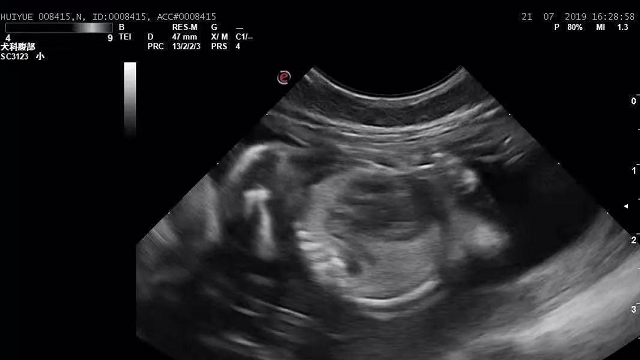

杜佳楣的一句话让夏月峰睡意全无,他不得不承认,妻子这个办法的确是对女儿最好的办法,可是妻子已经37岁,并且在萱萱出生之前,第一个孩子还胎死腹中。